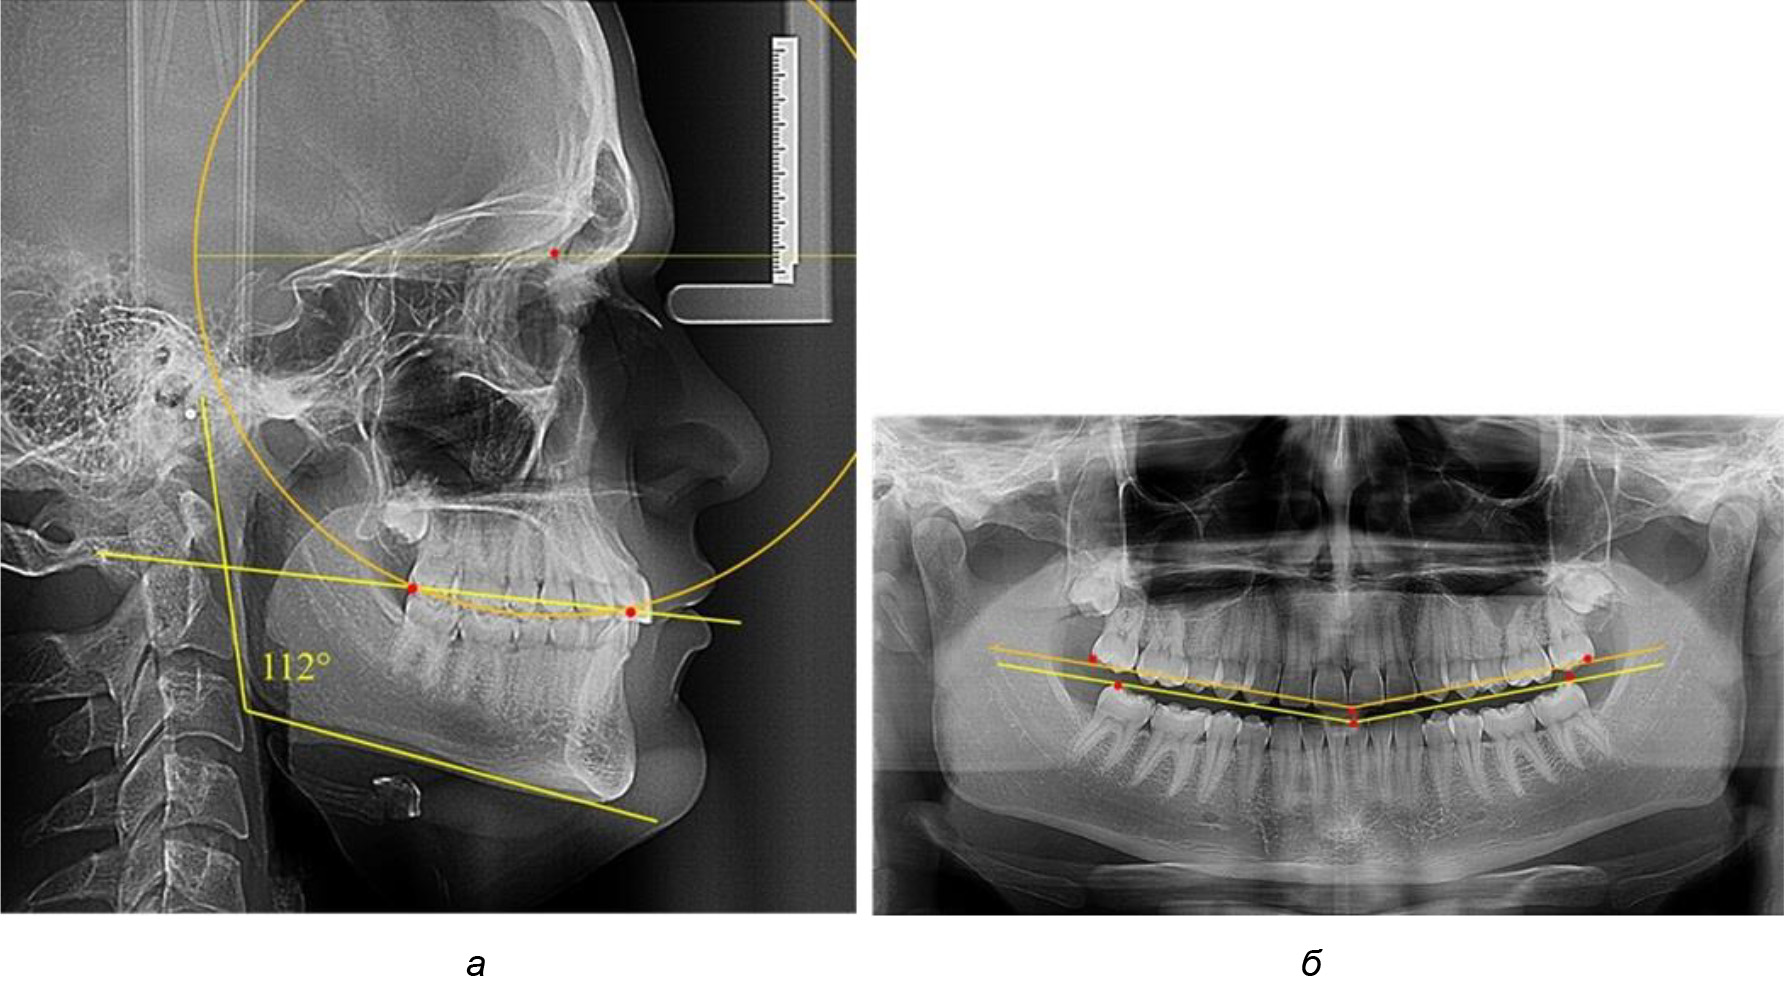

На рентгенограммах людей 2-й подгруппы (30 человек с нейтральным типом роста) величина угла нижней челюсти в среднем составила (120,34 ± 2,19) ° и характеризовала нейтральный тип нижней челюсти.

Глубина кривой Spee в среднем по 2-й подгруппе составил (3,54 ± 0,58) мм, что было незначительно меньше, чем при анализе аналогичного показателя 1-й подгруппы.

Достоверных различий с показателями, полученными при анализе ТРГ и ОПТГ, нами не отмечено (р ˃ 0,05). Деление величины радиуса круга к длине окклюзионной линии составило 1,612 ± 0,02, что, так же как и в 1-й подгруппе, было близким по значению к числу Фибоначчи (1, 618).

Рис. 3. Особенности кривой Spee на ТРГ (а) и ОПТГ (б) при нейтральном типе роста нижней челюсти